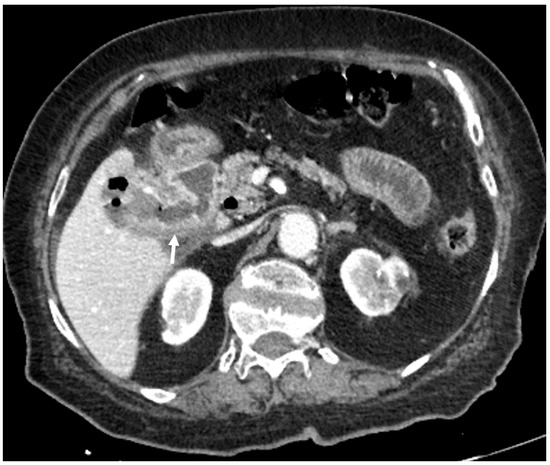

| F, 82 | 25 | III | Laparoscopically assisted enterolithotomy | 95 | Ileum | 3 × 3 cm | 3 | 14 | Good: recovery |

| F, 48 | 40 | III | Laparoscopically assisted enterolithotomy | 70 | Ileum | 3 × 4 cm | - | 10 | Good: recovery |

| F, 85 | 47 | IV | Laparoscopically assisted enterolithotomy | 60 | Ileum | 4 × 3 cm | 12 | 13 | Good: recovery |